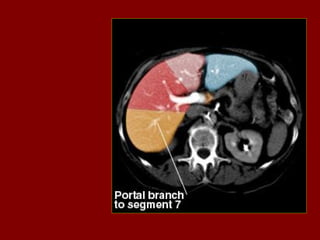

Cissura transversa(horizontal)

Cissura vertical

Ramo

Portal

segmento 3

principal